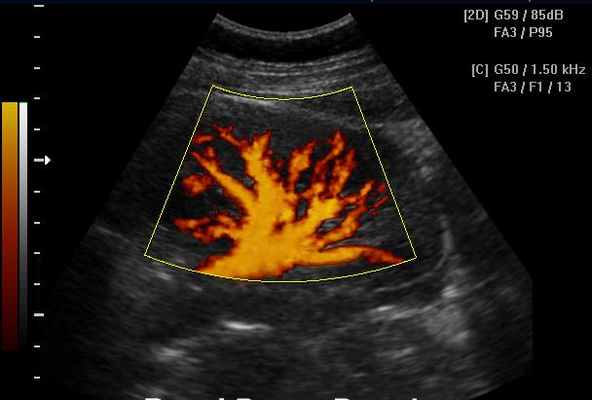

PDI (CDE, CPA, PDF, PD, PF, ЭДК и т.д.) – режим ЦДК «энергии» допплеровского спектра

Режим «энергетического» допплера является модификацией режима ЦДК и отличается от него тем, что режим ЭДК отражает движение в исследуемой области и его интенсивность, но информация о скорости и направлении при этом отсутствует. Режим ЭДК обладает практически полной независимостью от величины допплеровского угла.

Основное преимущество данного метода состоит в том, что режим ЭДК позволяет кодировать низкоскоростные потоки с значительно более высоким качеством, нежели в режиме ЦДК. Основной недостаток – большая чувствительность к любому движению, как датчика, так и исследуемой структуры.